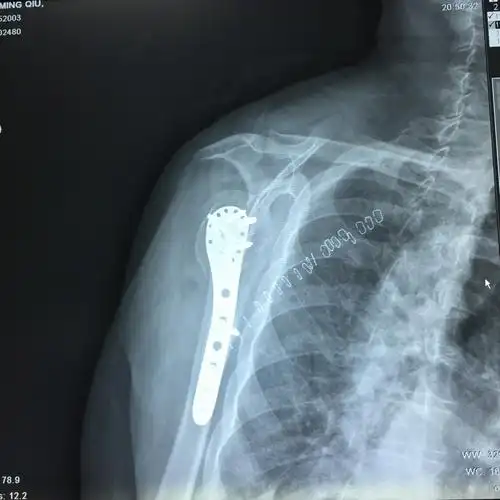

肩胛骨正侧位片与冈上肌出口位片投照要点*广东省中医院大学城运动